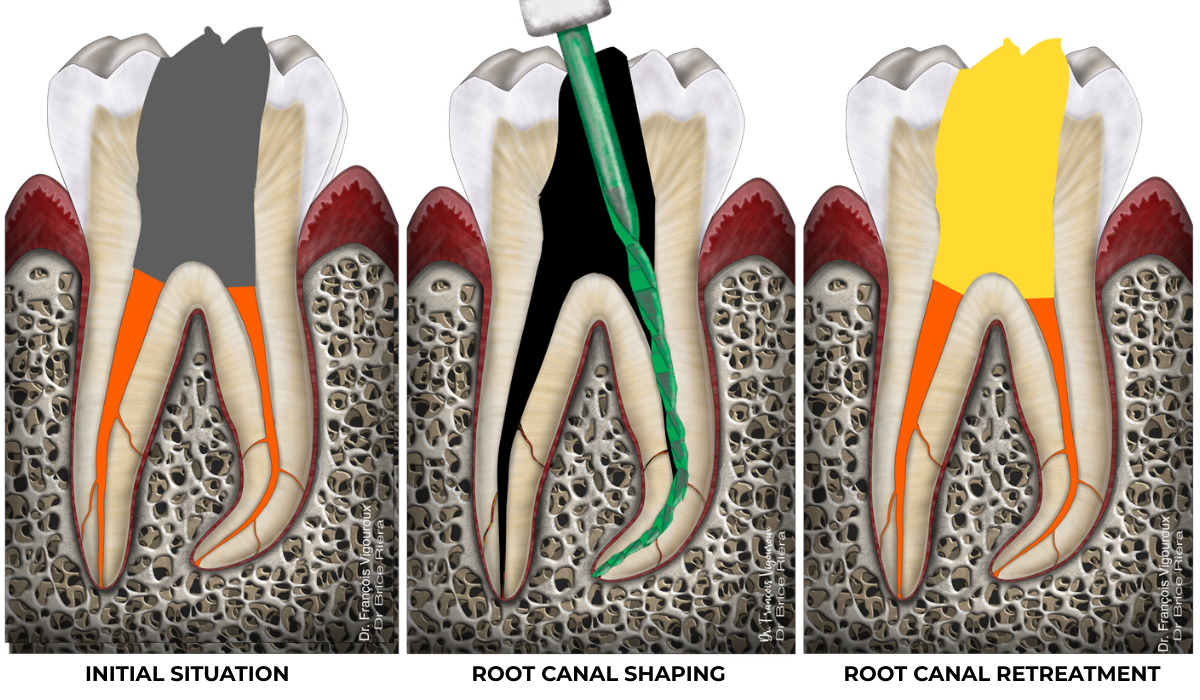

Root canal retreatment

A tooth may already have undergone root canal treatment. However, in some cases, this treatment needs to be carried out again. This is known as root canal retreatment.

A few examples of reasons why root canal retreatment may be required:

- A new restoration or prosthetic treatment (inlay, onlay, crown, etc.) is planned.

In the same way that a house requires its foundations to be made sound before reconstruction, a tooth may require root canal retreatment when a new prosthetic restoration is indicated. This applies whether or not an apical lesion is present.

- An intra-canal infection is present despite the existing root canal treatment and is causing an apical lesion.

Clinical case

Root canal retreatment: 80–95% success rate